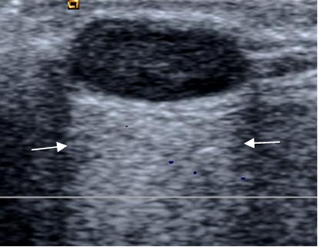

Pueden ser dolorosos y causar sintomatología por compresión de estructuras (Sindrome del carpo, del tarso, etc.). En ecografía son anecoicos, aunque puede ser lobulados y con septos. En la TAC son hipodensos y con señal variable en RM según su contenido, con septos y borde hipointensos en T2. Ej: Quiste de Baker, bursitis, quistes parameniscales. (Fig 218 A, B y C).

Fig 218 C. Sindrome del tarso.

A: Rx AP. Prominencia de tejidos blandos por debajo del maléolo interno (Flecha delgada), que erosiona en calcáneo. (Flecha gruesa).

B: RM axial y C: RM sagital en T2. Lesión ovalada, de consistencia líquida, en relación con el tendón del tibial posterior, que ocupa el canal del tarso, por ganglión.